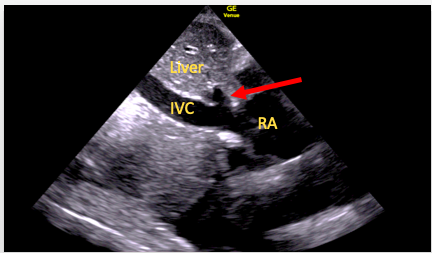

Subcostal Inferior Vena Cava View

The SC four-chamber view should again be obtained, with the right atrium in the center of the screen and a 90° anti-clockwise rotation of the transducer performed. An element of tilting may then be required to bring the IVC into view and to visualize its entry into the right atrium (Figure 12). It is important not to mistake the IVC for the aorta or a hepatic vein. Techniques to avoid this include:

- Visualization of the IVC joining the right atrium

- Visualization of the hepatic vein as it joins the IVC

- Transverse (short axis) assessment of the IVC as it lies adjacent and to the right of the aorta

- The use of color flow and pulsed wave Doppler to assess flow pattern and direction.

Figure 12. SC IVC view. Here the right hepatic vein (arrow) can be seen to join the IVC just before it enters the right atrium (RA)